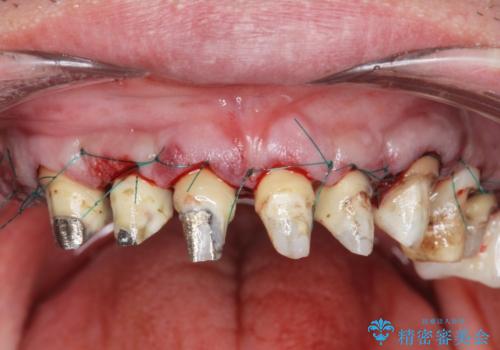

- 「セラミック治療を他院で受けたが、それ以来歯ぐきが腫れ違和感がある、改善してほしい。」と歯ぐきの状態改善を希望され来院されました。

歯周組織検査を行うと歯ぐきからは容易に出血し、X線検査より歯とセラミッククラウンの適合が悪い(ピッタリと合っていない)状態が示唆され、歯ぐきの炎症を惹起している状態でした。

セラミッククラウンを除去し仮歯を装着し、歯周外科手術を行い歯ぐきの状態を改善したのち、適合の良いセラミッククラウンを再作製をする治療計画としました。

- 90.2万円(ジルコニアクラウン×6・仮歯×6 ・歯周外科手術)費用は治療当時の料金となります